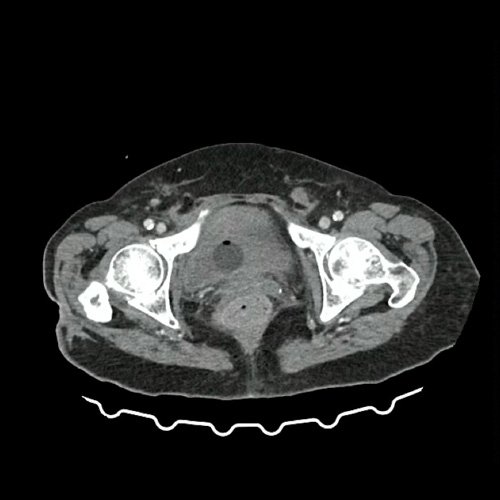

Anexo 2: TAC de pelvis con contraste, corte axial. DÍA 0 06/09/2025

En dicha unidad se realizó tomografía con hallazgo de lesiones hipodensas en ambos riñones (descritas como probable origen inflamatorio-infeccioso), líquido libre periuterino con reticulación de grasa locorregional. Por hallazgo de hematometra se solicita interconsulta a Servicio de Ginecología, quienes descartan conducta quirúrgica de urgencia.